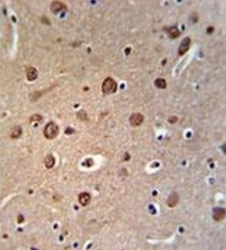

- Main image

- Experimental details

- Formalin fixed and paraffin embedded brain tissue reacted with FAM156A Antibody (C-term) Cat.-No AP51500PU-N followed by peroxidase conjugation of the secondary antibody and DAB staining.